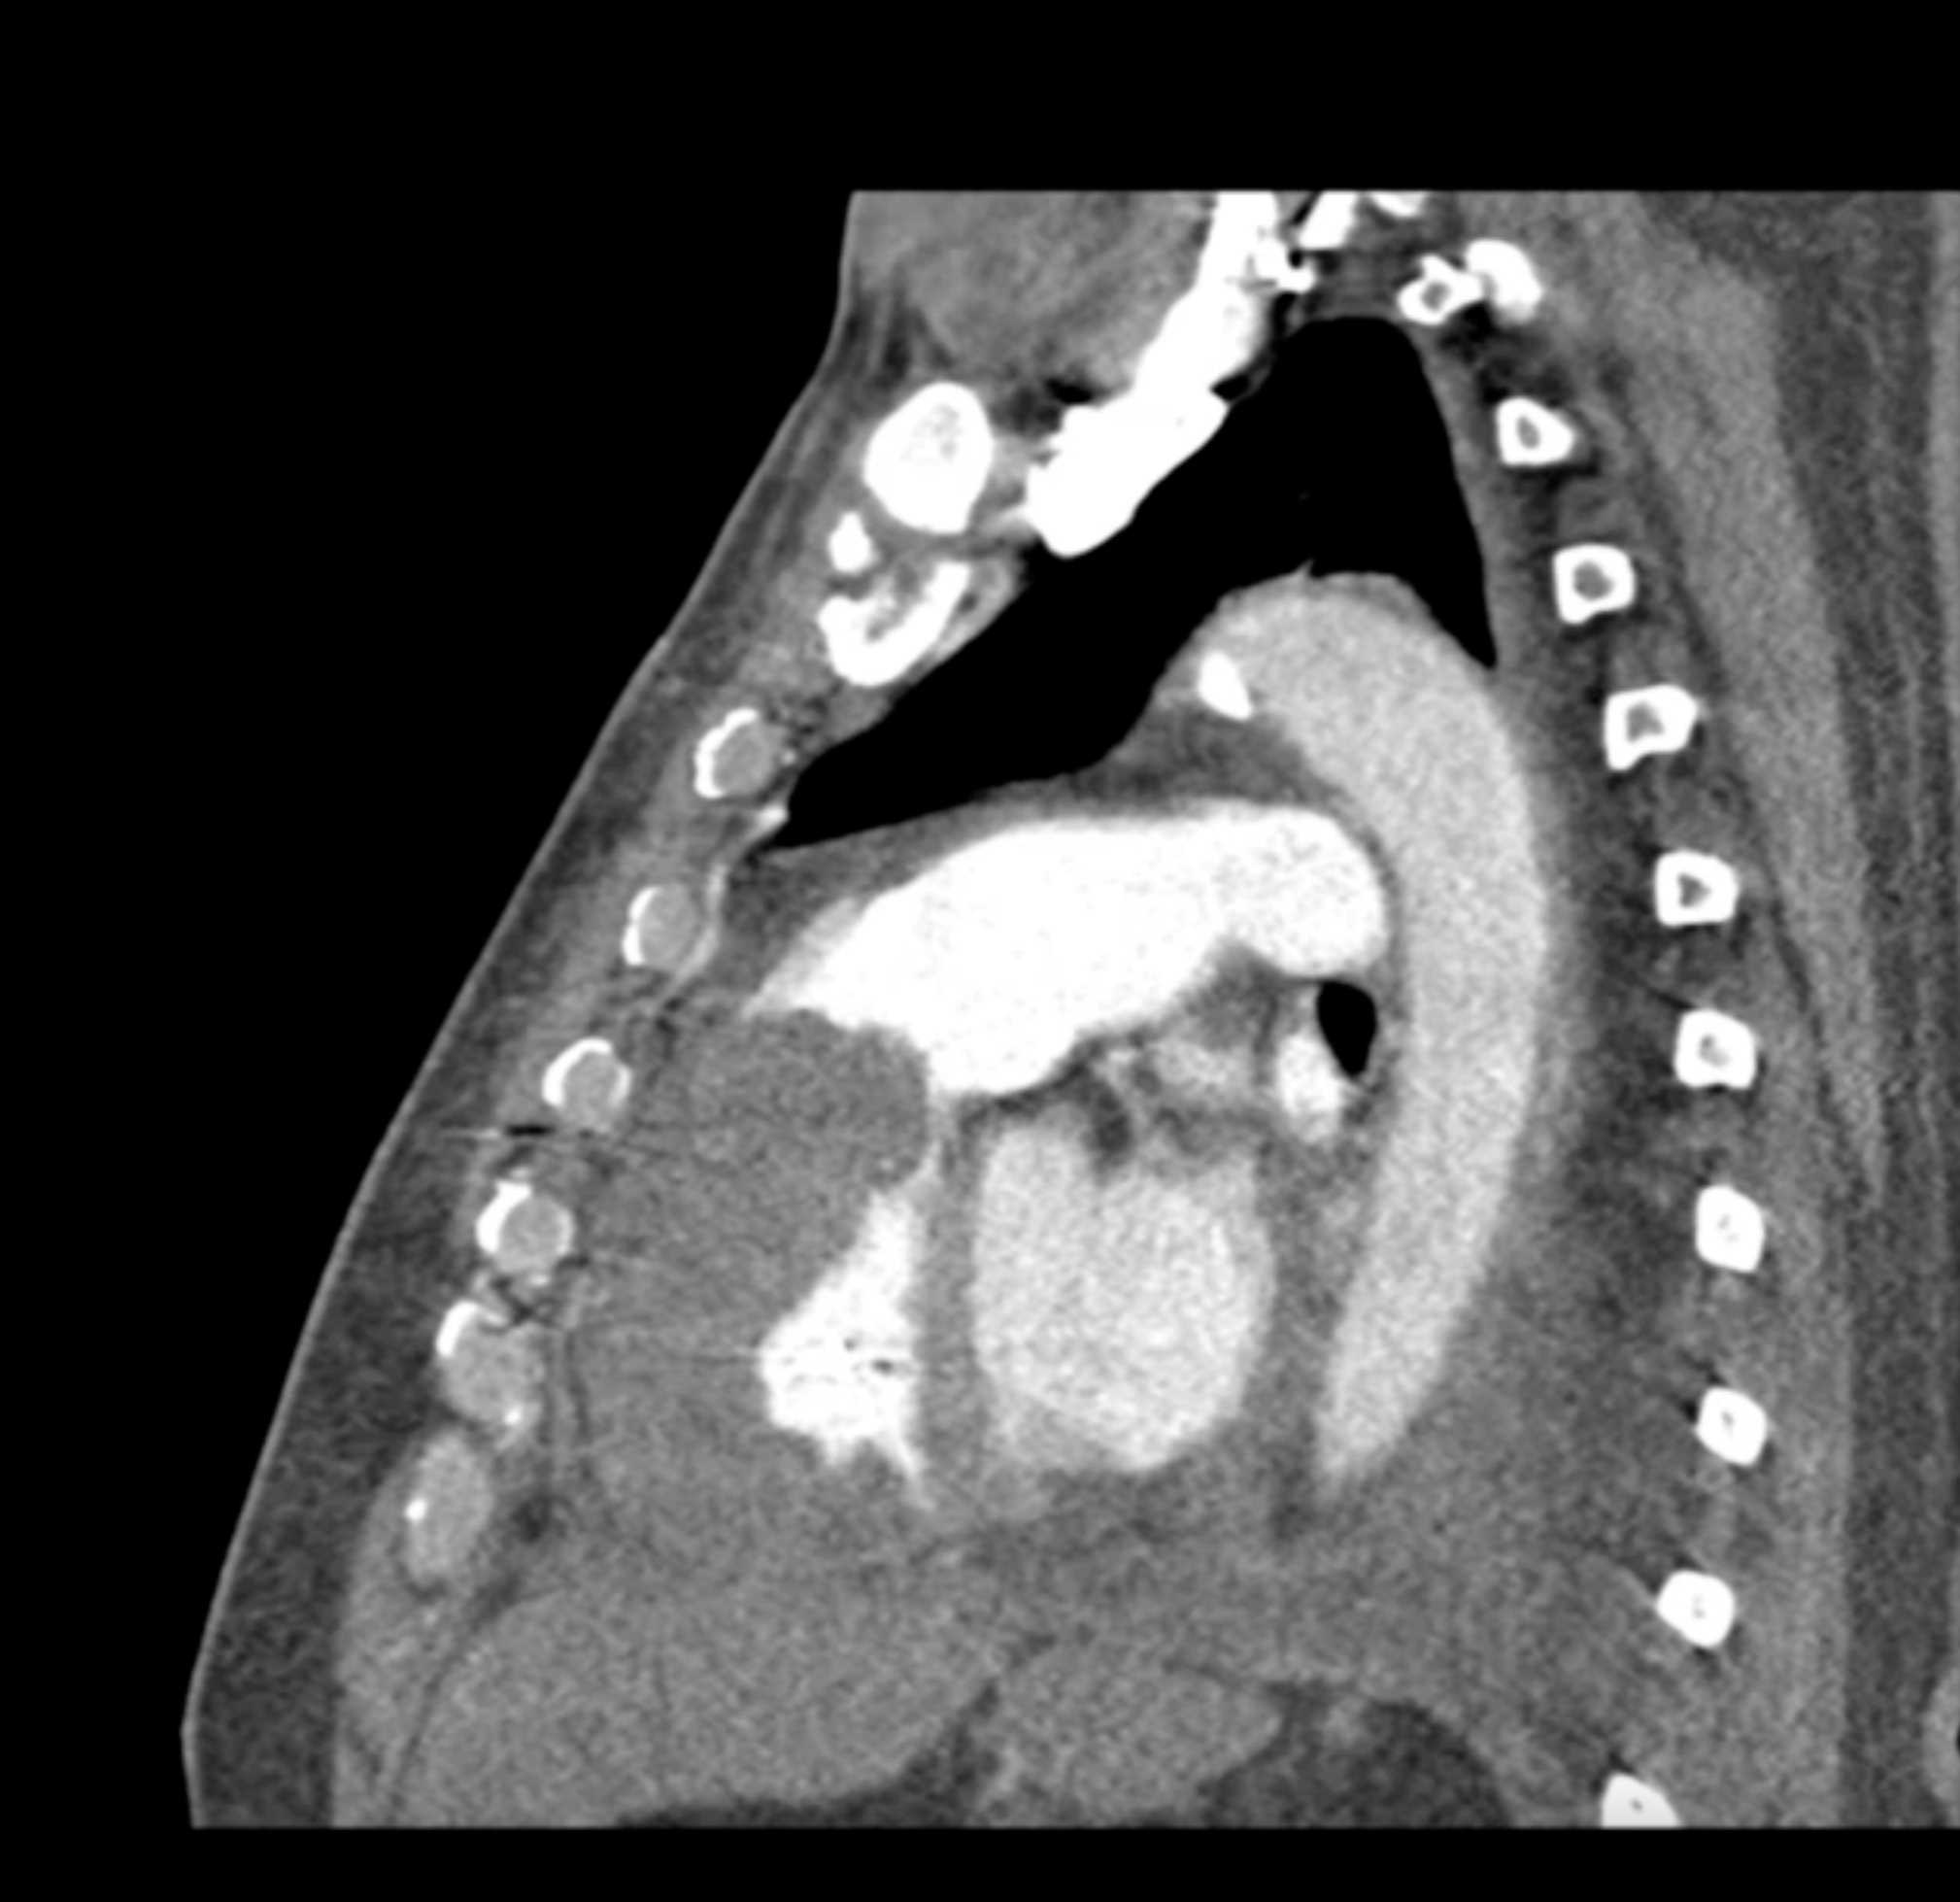

Primary Spindle Cell Carcinoma of the Right Ventricle